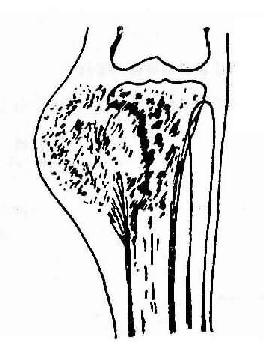

3.混合型骨肉瘤(Osteosarcomamixed type) 其X线表现为介于上述两型间,有不同程度的骨膜反应及骨质改变(图2-64)。

胫骨上端骨肉瘤(混合型)

图2-64 胫骨上端骨肉瘤(混合型)显示软组织肿块内团状瘤骨,有三角型骨膜反应,胫骨上端有瘤骨增生及溶骨破坏。